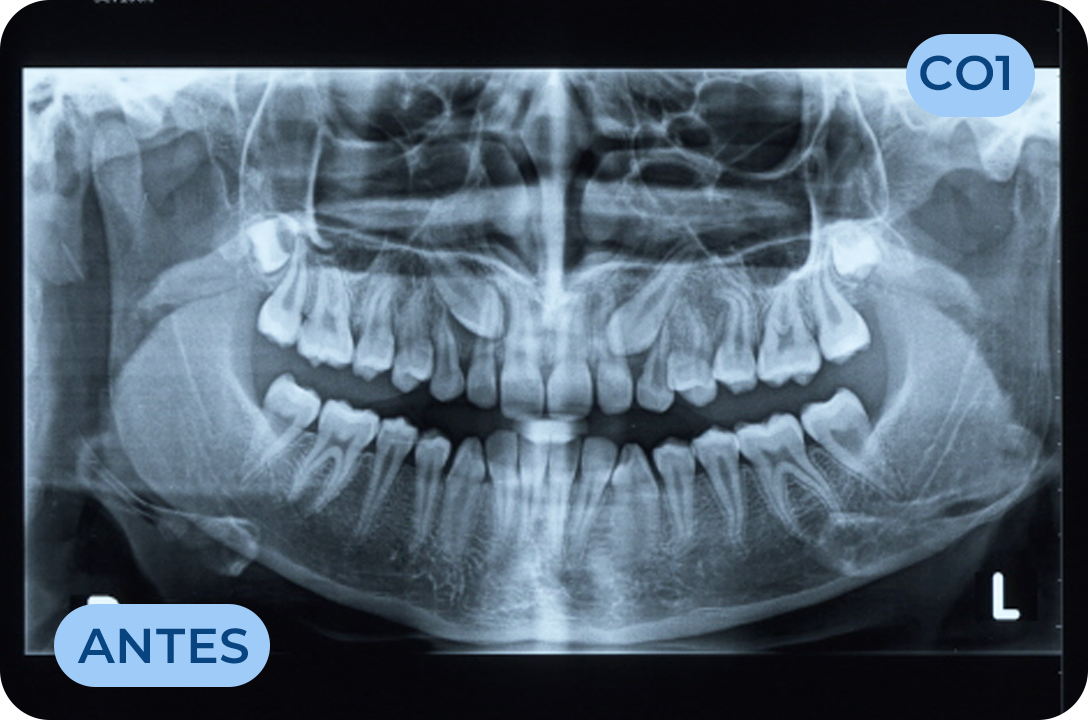

Ortodontia

É a especialidade da Medicina Dentária que se debruça sobre o estudo e correção das más posições dentárias e dos maxilares. Atualmente é possível tratar pacientes de todas as idades, no entanto a 1ª consulta deve ser realizada ainda na infância para intercetar eventuais problemas de desenvolvimento esquelético e funcional.

Cirurgia Oral

Área da medicina dentaria que diagnostica e trata as lesões e anomalias dos dentes, tecidos moles e estruturas anexas aos maxilares. A extração de dentes irrecuperáveis, dentes inclusos, supranumerários, frenectomias (eliminação dos freios), biopsias, exérese de quistos e outras lesões dos tecidos orais, fazem parte do seu vasto campo de execução.